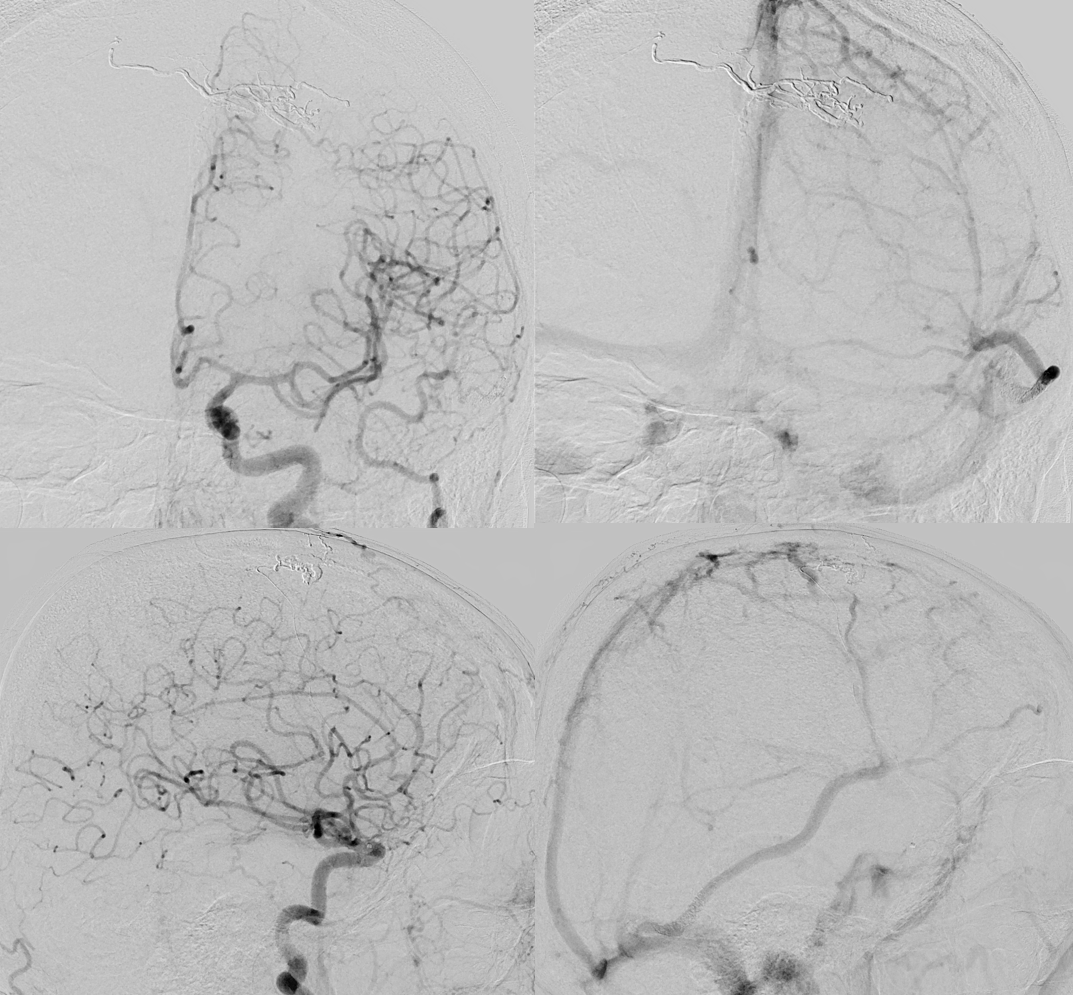

Onyx

It is important to have control from other side — and another access for that. Needed more onyx

Done